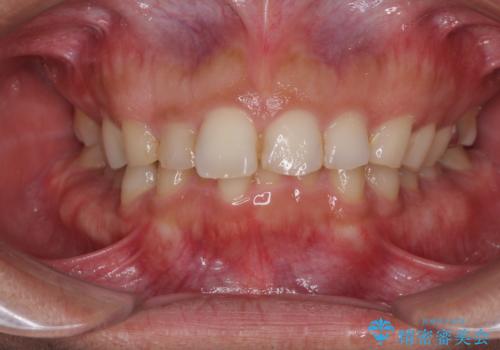

[インビザライン ライト] 短期間(3.5ヶ月)で終わるマウスピース矯正

![[インビザライン ライト] 短期間(3.5ヶ月)で終わるマウスピース矯正の症例 治療前](https://seimitsushinbi.jp/wp/wp-content/uploads/2020/02/C3-500x350.jpg?v=1580813654)